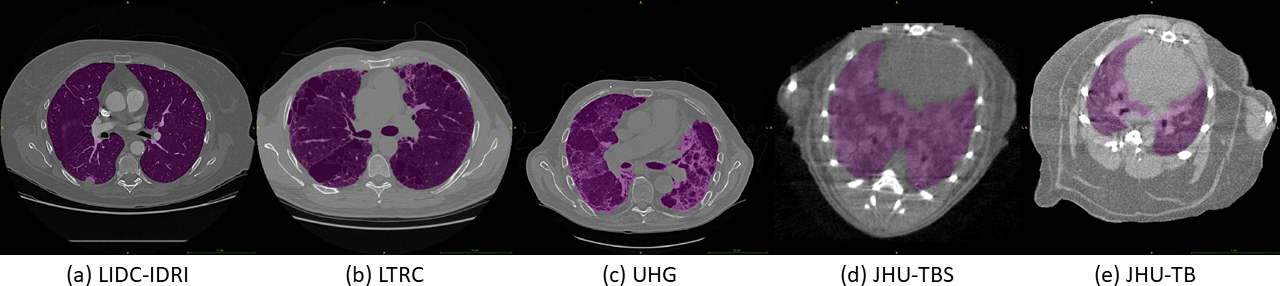

Fig. 3: Example scans with ground-truth masks (magenta) for each of the five datasets in this study.

Experiments were conducted on five pathological lung datasets, obtained from both clinical and pre-clinical subjects, containing nearly 200020002000 CT scans, with annotations by expert radiologists. An example typical scan with ground-truth from each dataset is shown in Figure 3. The three clinical and two pre-clinical (mice) datasets analyzed are as follows: